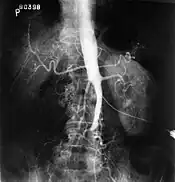

The physical examination usually shows weakened femoral pulses and a reduced ankle-brachial index. The diagnosis can be verified by color duplex scanning, which reveals either a peak systolic velocity ratio ≥2.5 at the site of stenosis and/or a monophasic waveform. MRA and multidetector CTA are often used to determine the extent and type of obstruction. Another technique is digital subtraction angiography which allows verification of the diagnosis and endovascular treatment in a single session.[1]

Angiography provides important information regarding the perfusion and patency of distal arteries (e.g. femoral artery). The presence of collateral arteries in the pelvic and groin area is important in maintaining crucial blood flow and lower limb viability. However, angiography should only be used if symptoms warrant surgical intervention.[1]